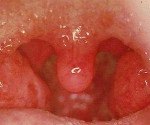

Агранулоцитарная ангина является септическим заболеванием, при котором на первый план выступают своеобразные изменения в зеве и крови. При этом заболевании наблюдаются грязно-серые налеты с некротическим распадом на миндалинах, язычке, на дужках, а иногда и на задней стенке глотки при одновременном сильном припухании шейных лимфатических узлов. В периферической крови отмечается отсутствие гранулоцитов с наличием лишь лимфоцитов и моноцитов.

Клиническая картина

Ассоциированные симптомы: Боль в горле. Высокая температура тела. Лейкоцитоз. Лимфоцитоз. Моноцитоз. Нейтропения. Озноб. Субфебрильная температура.